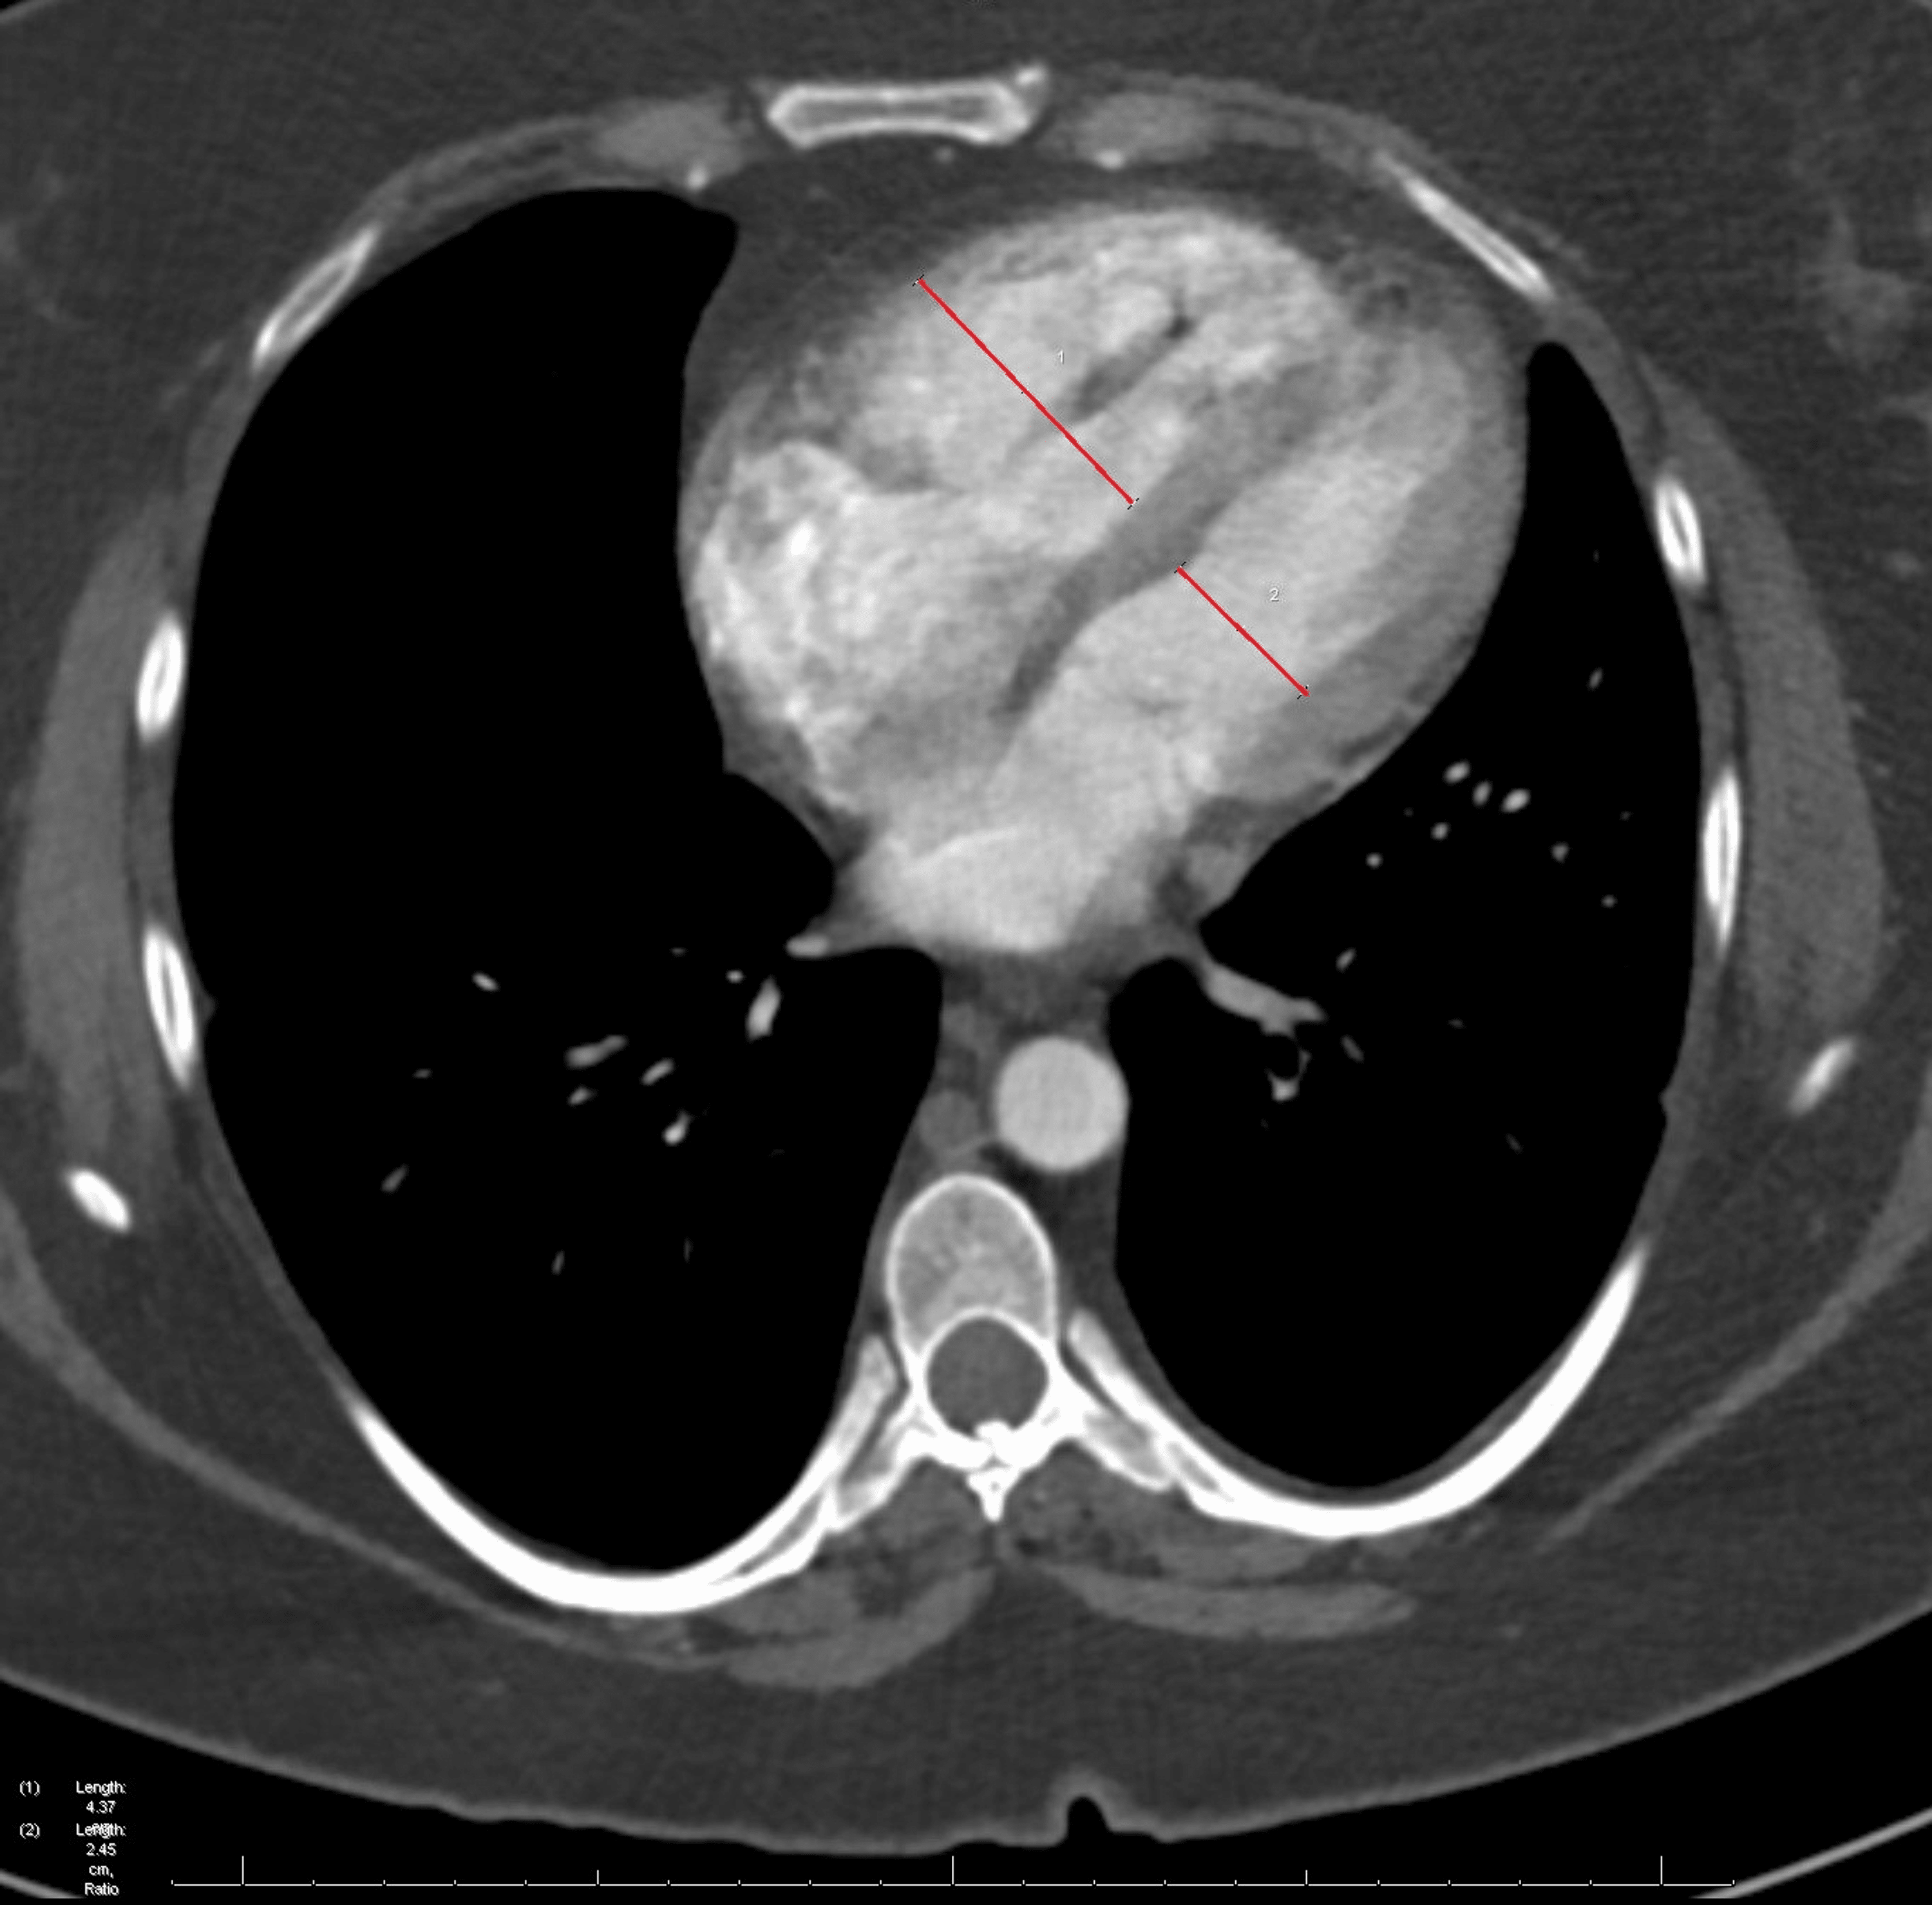

From www.semanticscholar.org

Figure 1 from Unique Case of Alpha 1Antitrypsin Deficiency Causing Protein S Deficiency Pulmonary Embolism Protein s deficiency is an inherited thrombophilia associated with an increased risk of thromboembolism. Subjects were regarded protein s deficient when protein s levels were <2.5th percentile of the controls. Conditions such as protein s deficiency, resulting from genetic mutations, are encompassed within this category of causative. Having this deficiency puts you at risk for a blood clot in your. Protein S Deficiency Pulmonary Embolism.